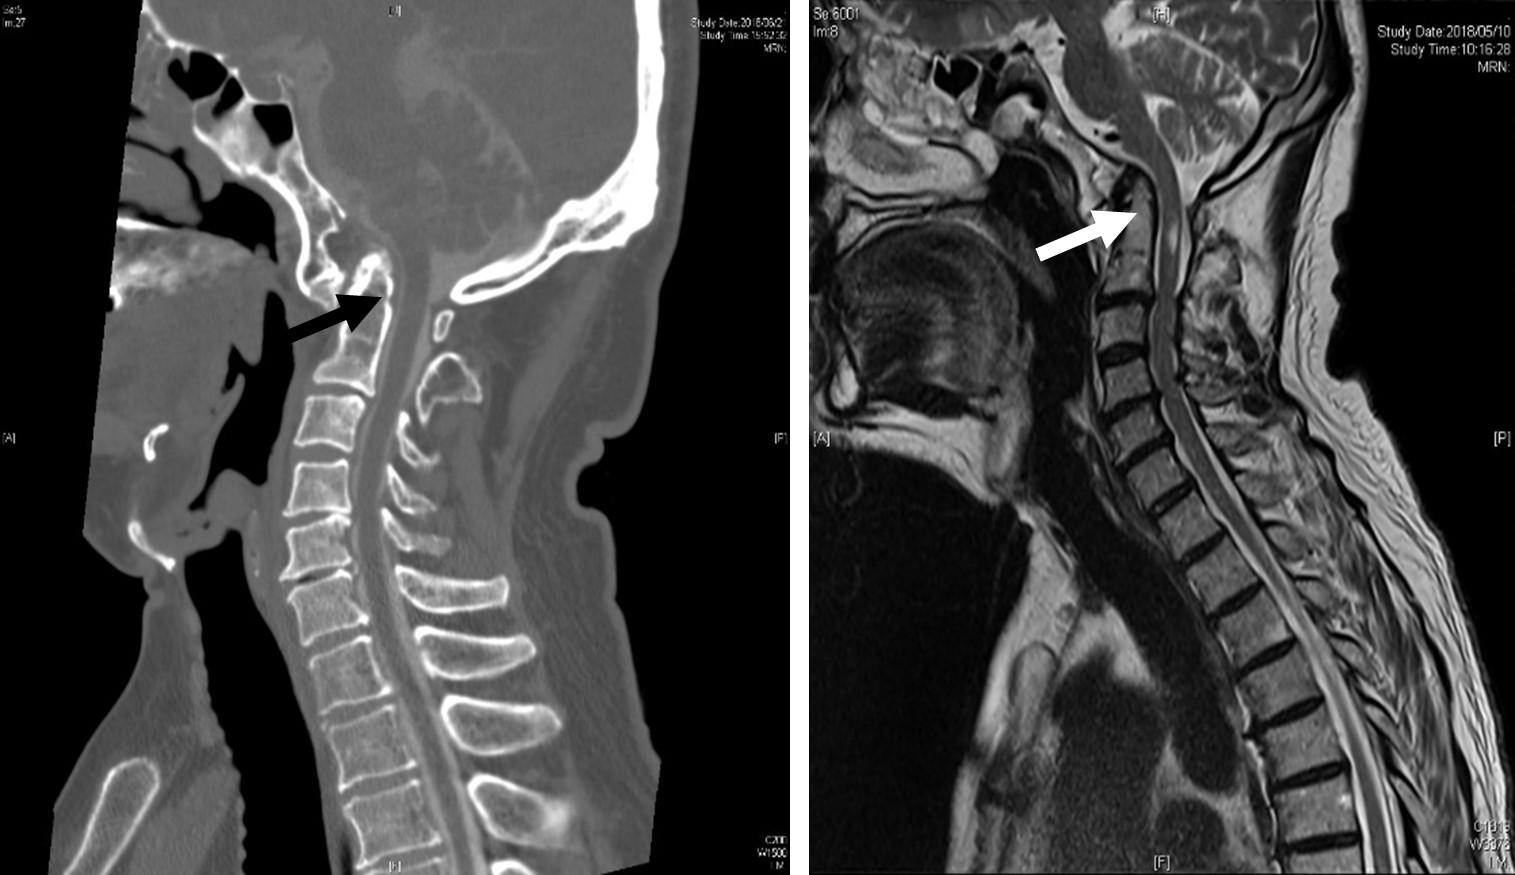

図 頭蓋底陥入症

(左)第2頚椎歯突起が頭蓋骨内に陥入し、延髄と脊髄を圧迫している。

(右)手術により神経の圧迫は解除されている